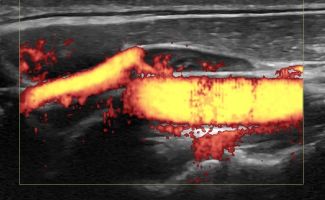

Το Υπερηχογράφημα Λεμφαδένων Τραχήλου προσφέρει μια εμπεριστατωμένη εικόνα των λεμφαδένων, με χρήση της προηγμένης τεχνολογίας των ειδικών κεφαλών υψηλής συχνότητας, Έγχρωμου Doppler, Power Doppler και B-Flow, καθώς και της Ελαστογραφίας. Με αυτές τις τεχνικές είναι δυνατή η γρήγορη και αξιόπιστη αξιολόγηση της μορφολογίας των λεμφαδένων και η αναγνώριση των χαρακτηριστικών τους με μεγάλη ακρίβεια.